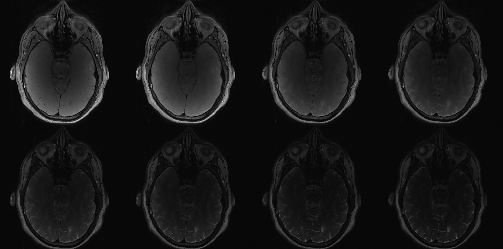

Chronic traumatic encephalopathy (CTE), formerly known as dementia pugilistica, is a neurodegenerative disease found in people who have had multiple head injuries.[1] Neuropathologically, CTE is characterized by atrophy of the cerebral hemispheres, medial temporal lobe, thalamus, mammillary bodies, and brainstem, with ventricular dilatation and a fenestrated cavum septum pellucidum.[2]

A similar thing occurs in your brain when you encounter a blow to the head. The brain is comprised of things called “neurons” which help regulate functions in the brain. When your brain encounters a significant impact, such as a punch to the head, proteins that hold these neurons together, Tau proteins, may start to fall off. [This would be like the sand falling off of your shoes]

The more and more blows a person receives to the head, the more and more these proteins will fall off. Since Tau proteins hold the neurons together, if they fall off, the neurons themselves will start to fall apart. If the neurons start to fall apart, a person’s brain functions will start to deteriorate. This degeneration of the brain is CTE.[5]